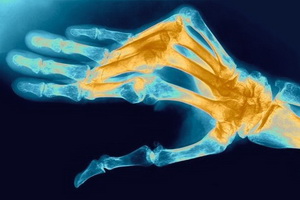

Ревматоидный артрит (РА) – аутоиммунное заболевание неизвестной этиологии, характеризующееся неуклонно прогрессирующим деструктивным поражением суставов и широким спектром внесуставных (системных) проявлений.